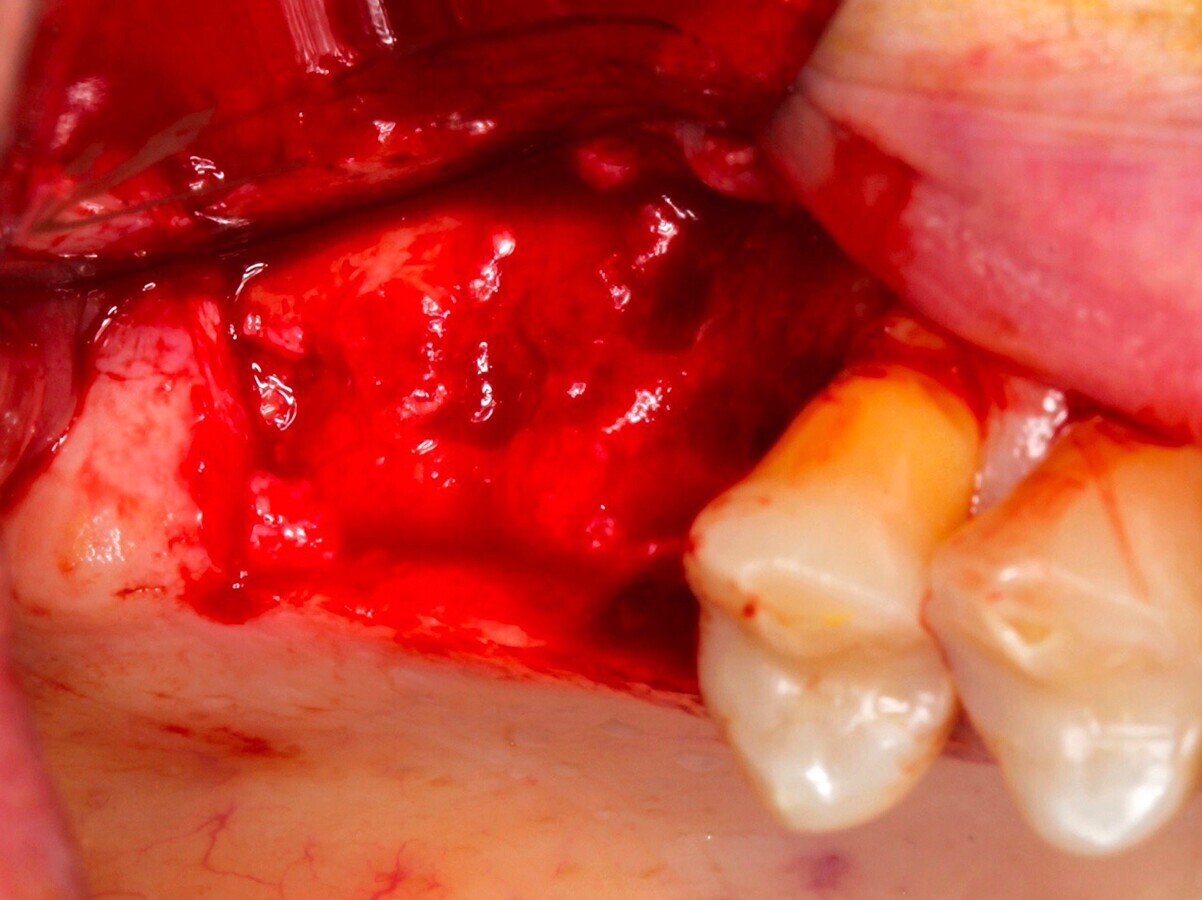

Fig. 14 Figura 14

1. Elevación del colgajo mucoperióstico a espesor total con periostotomo exponiendo el defecto en su totalidad.

2. Determinación de las dimensiones del injerto.